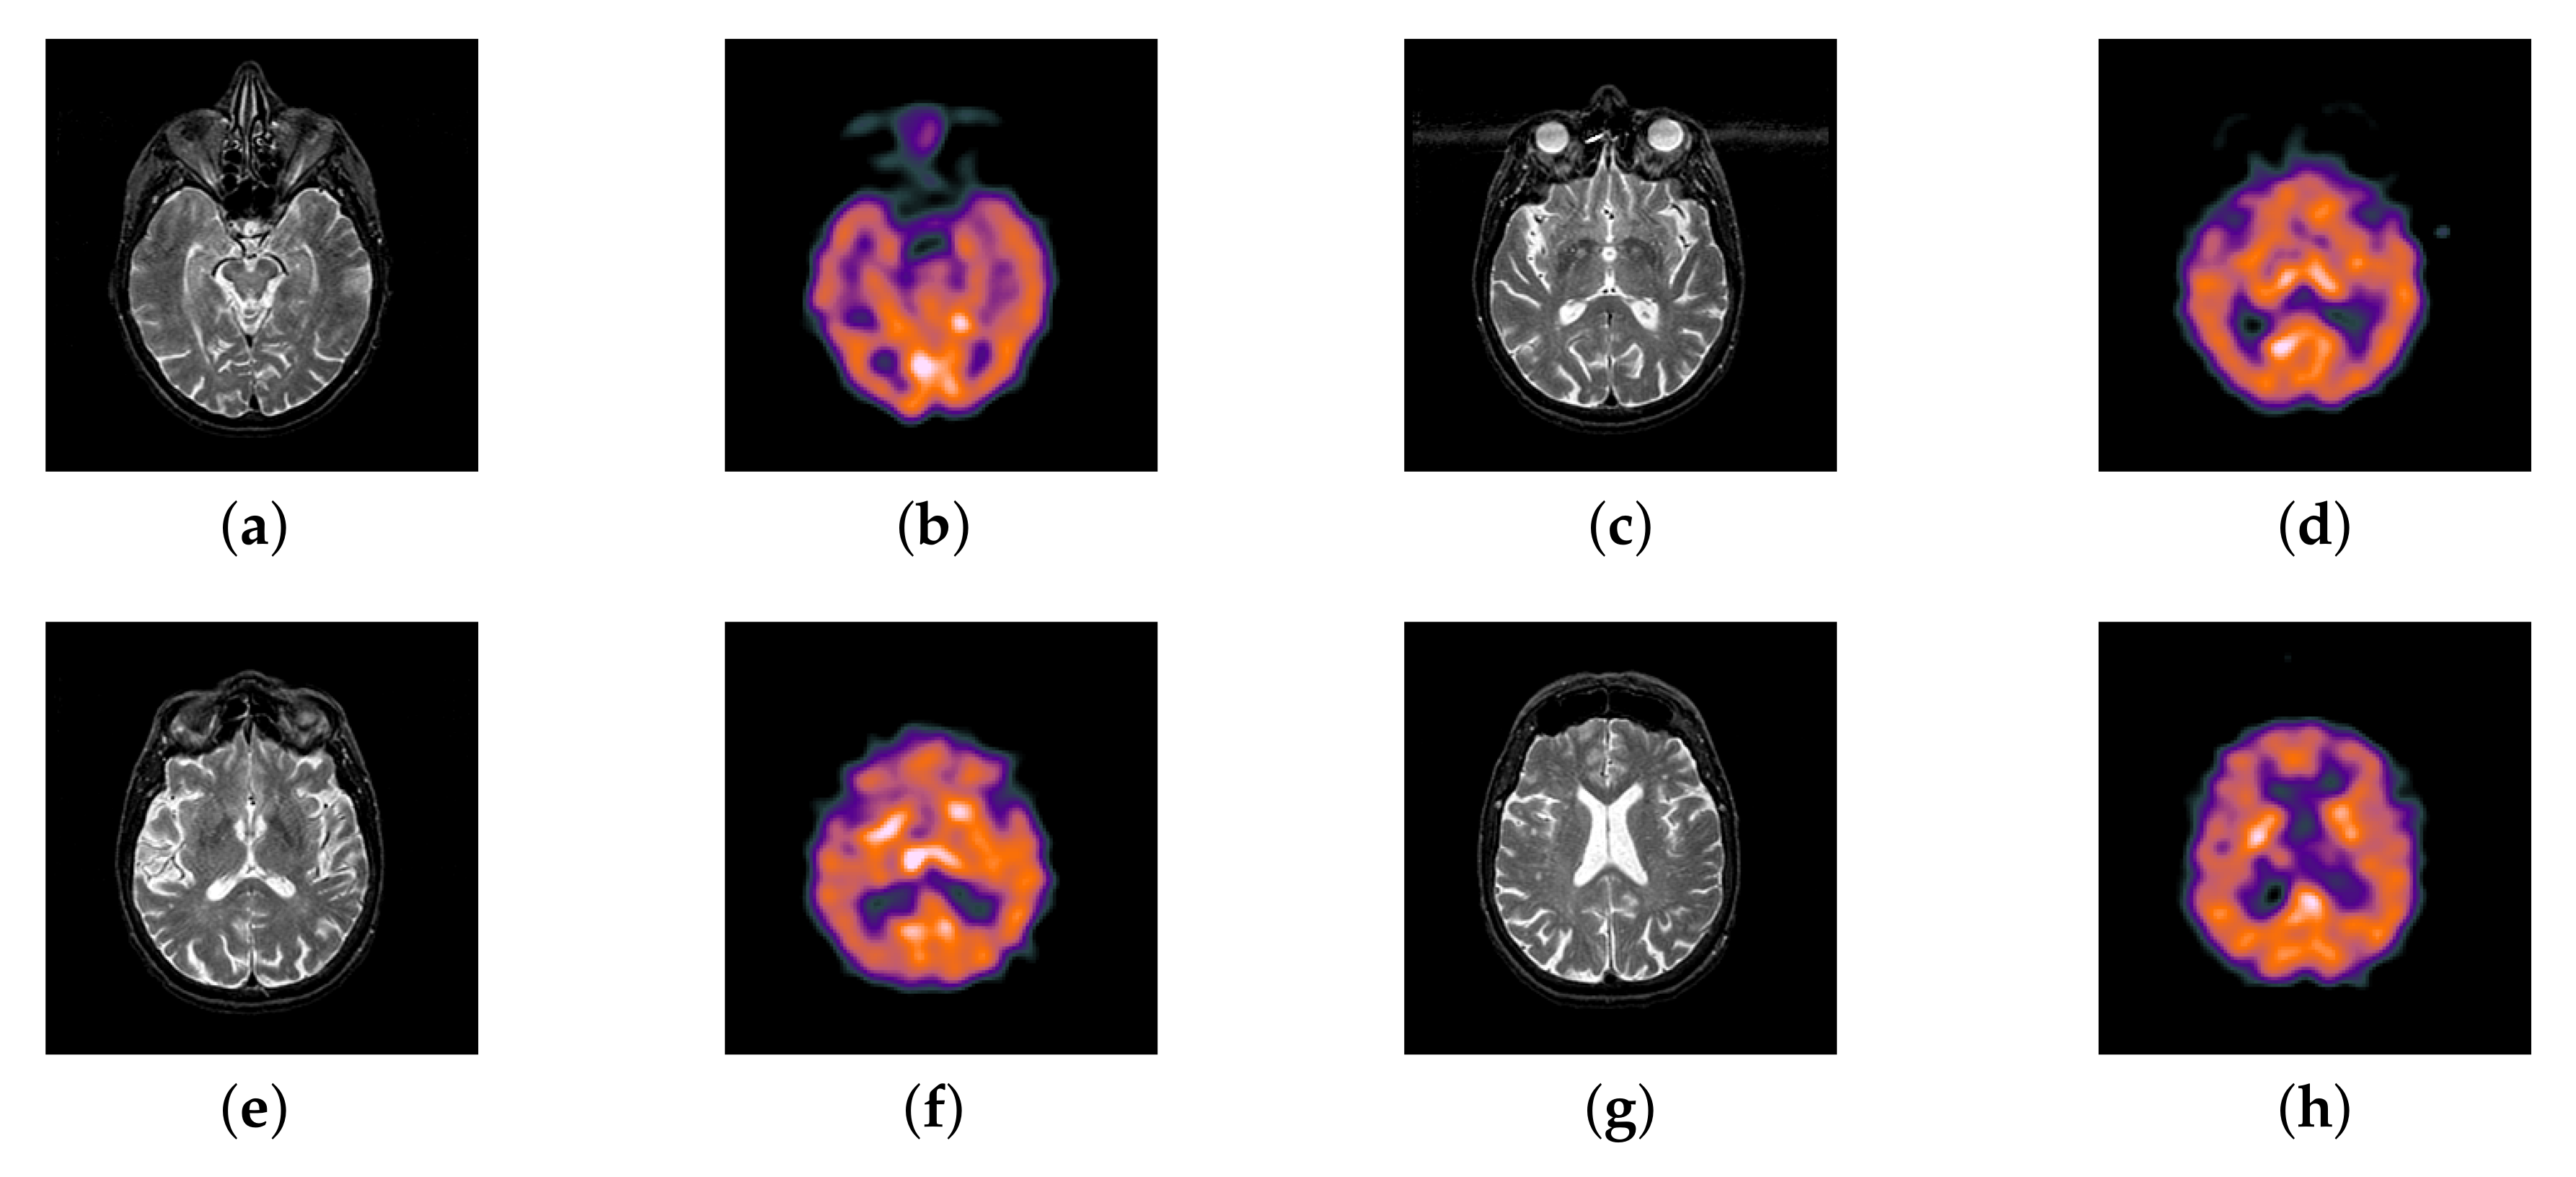

In previous intuitionistic fuzzy sets, scholars usually set to the order of 10 squares. Here, we set to 200, 300, 400, 500, 600, 700, and 800, respectively. Then, the image enhancement experiment is carried out, and the experimental results are shown in Figure 6. According to the results, we can find that, when is set to 500, the result is better than others.

Figure 6.

Source image and its image reconstructed by different algorithms): (a) Source image, (b) = 200, (c) = 300, (d) = 400, (e) = 500, (f) = 600, and (g) = 700, (h) = 800.